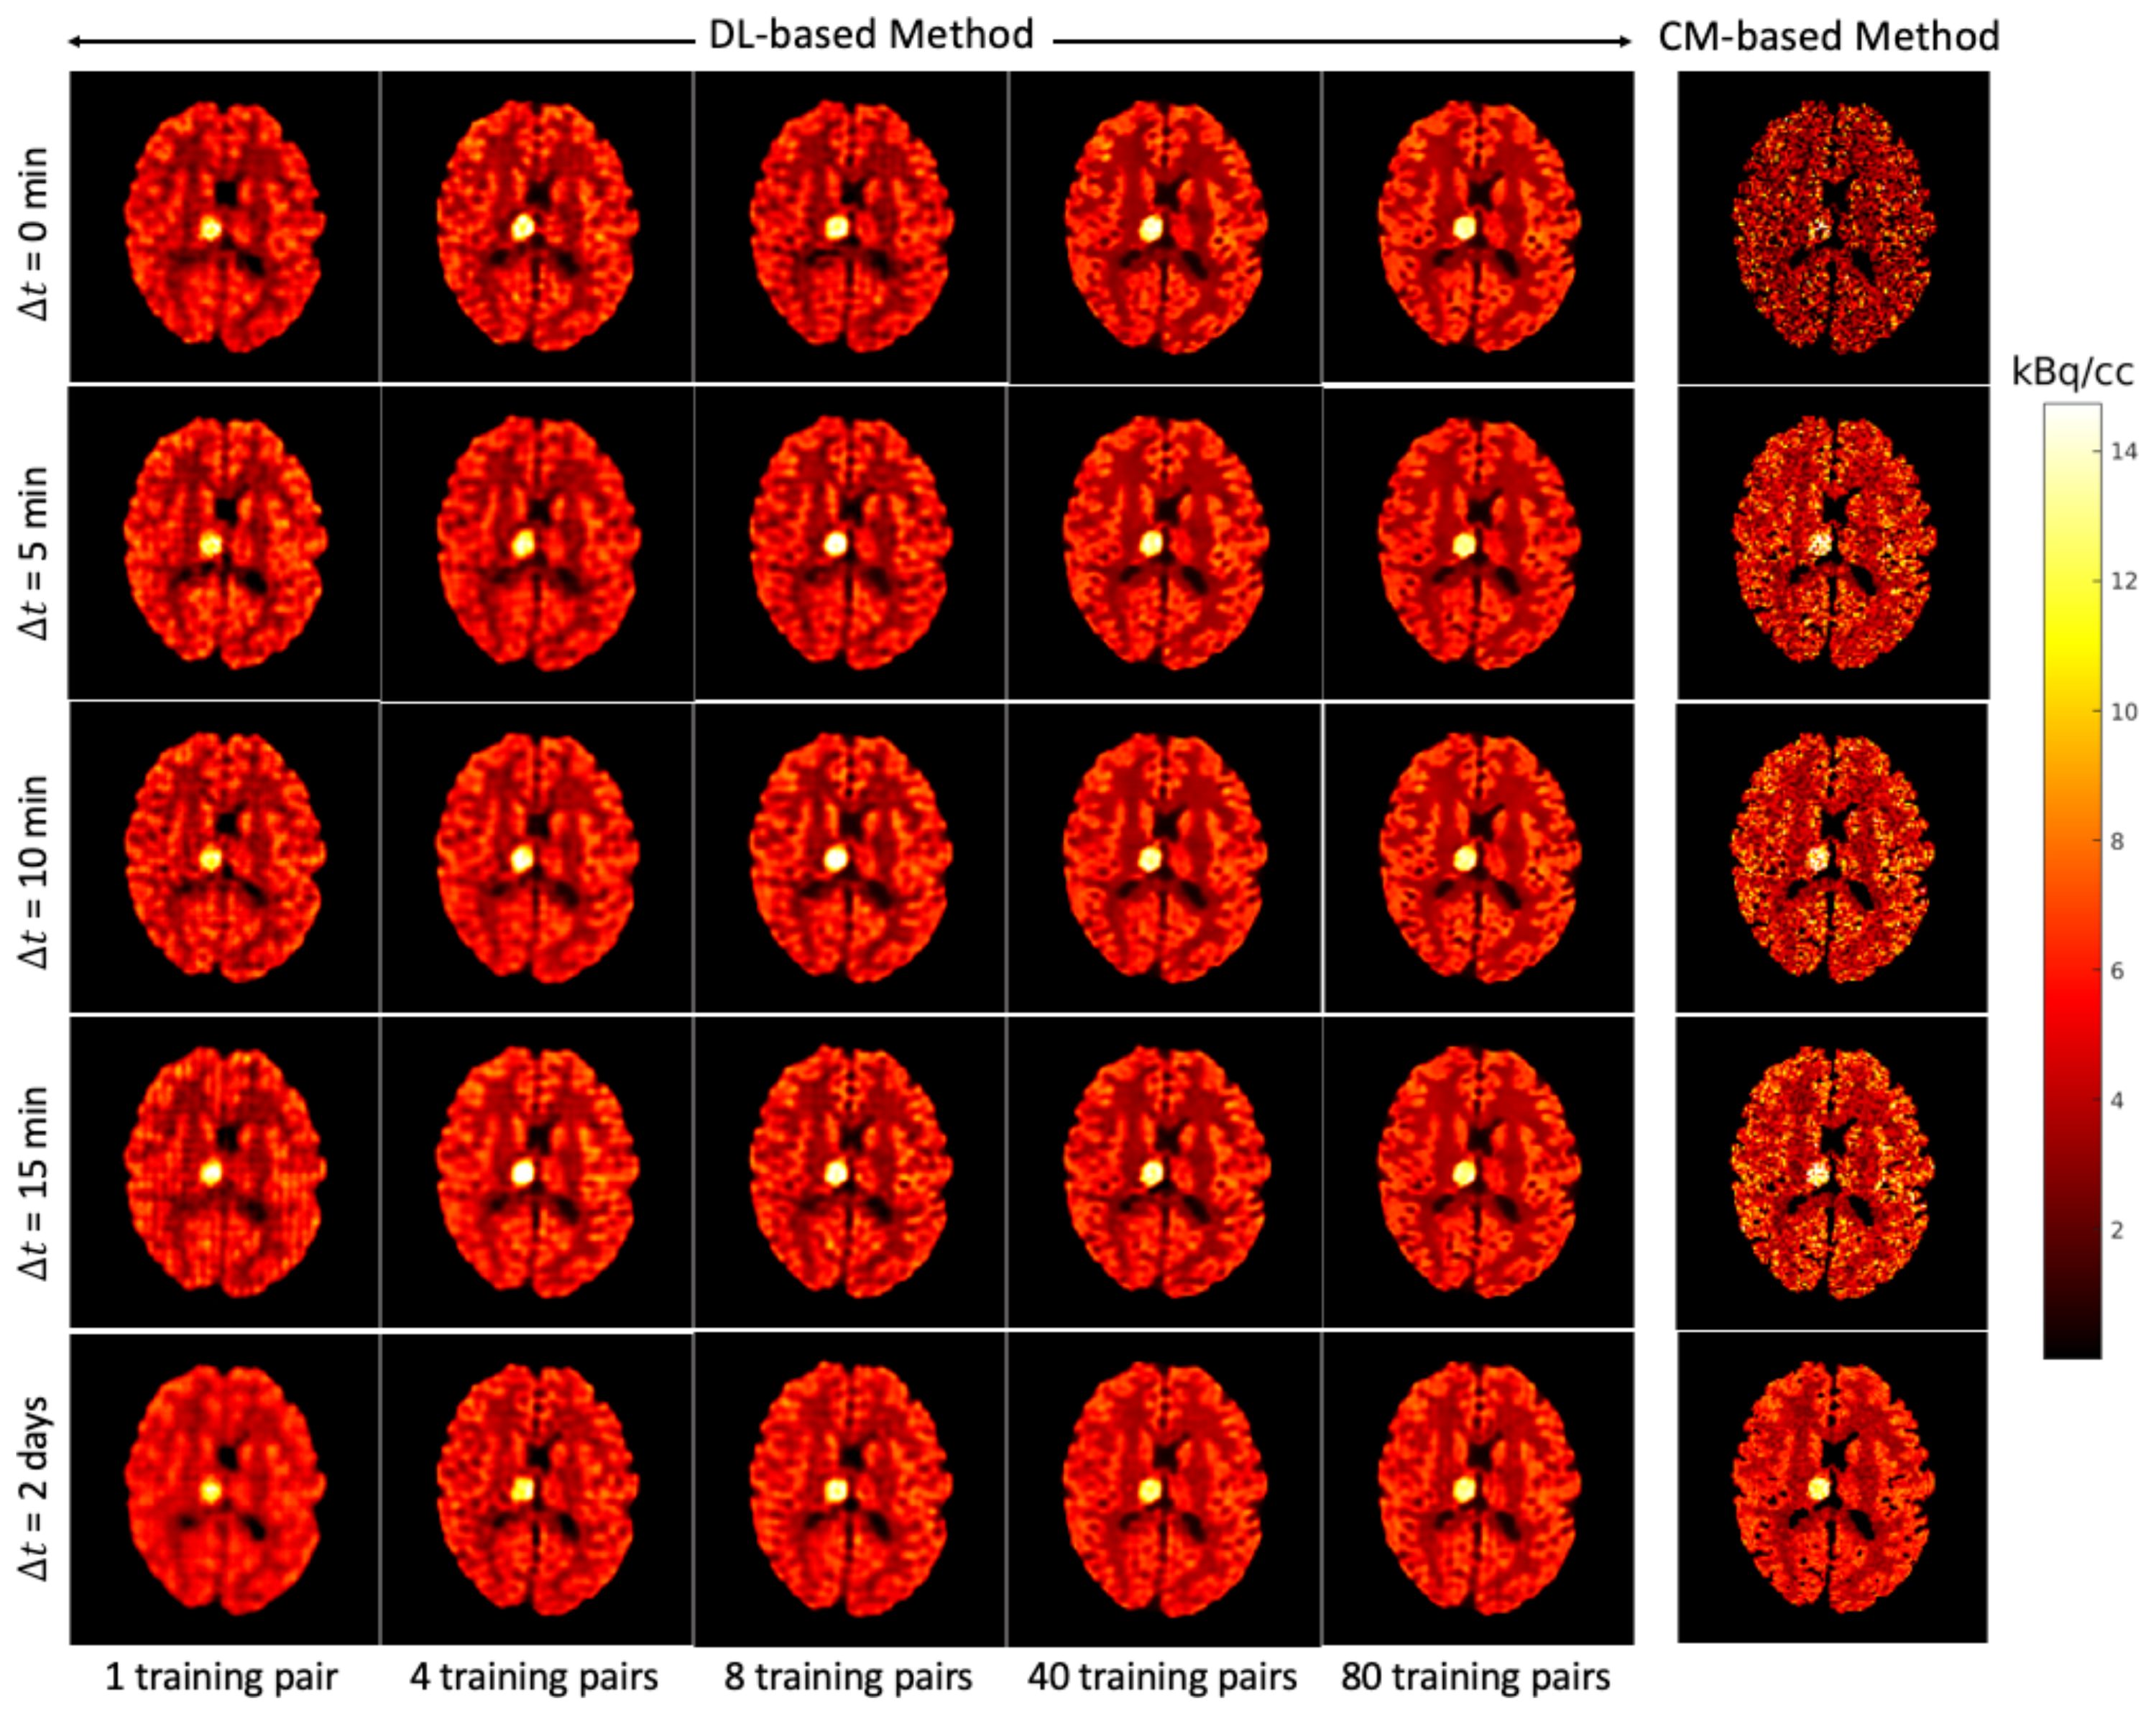

Figure 7 shows for each that the average NRMSE decreases and that a smaller SD is obtained in the test set as the number of training pairs increases from 1 to 80. This is consistent with the visual impression of the separations obtained by the DL-based method, as shown in Figure 8 and Figure 9. The first to fifth columns display the separated static single-tracer images (activity distributions) based on different numbers of training pairs (for plotting only, we limit the colour scale of the figures to fall within the same range as the reference images in Figure 6b for and Figure 6e for , respectively). Although all cases successfully recover the separated images, using more training pairs results in higher separation performance in terms of recovering the tumour regions, shapes and low contrast of the white and grey matter for . Figure 10a,c also suggest that the more training pairs used, the better the average NRMSE, which is in line with the results shown in Figure 7. With 80 training pairs, the DL-based method achieved average NRMSE values for FDG and MET of ∼15% and ∼12%, respectively, for the test set across all (see the magenta lines in Figure 10a,c).

Figure 9.

Brain phantom (whole brain region): the static images recovered using the DL-based method (Columns 1 to 5) and the CM-based method (Column 6).

A test example of the separated images using the CM-based method is shown in the last column of Figure 8 (FDG) and Figure 9 (MET) for different . Compared to the results obtained from the DL-based method, the separated images using the CM-based method are much noisier because the model fitting (4) may fall into local minima even when the noise level is low. Although several strategies, such as using differing initial values or an exhaustive search algorithm [22], have been suggested to reduce local minima, their use in clinical practice is challenging because of their high computational cost.

4.3. DL-Based Method and CM-Based Method Comparison

The separation results between the DL-based method and CM-based method applied to the reconstructed dynamic dual-tracer noisy MLEM images were compared. For = 0, 5, 10 and 15 min, Figure 8 and Figure 9 show that in terms of visual assessment the CM-based method produces much nosier separated images than the DL-based method. This observation is consistent with better average NRMSE values of the DL-based separation results as illustrated in Figure 10. When using only 1 training pair, the DL-based method achieved high average NRMSE values across all (∼25% for FDG and ∼22% for MET). However, it nevertheless produces better average NRMSE values for = 0, 5, 10 and 15 min when compared to the separation results using the CM-based method. In fact, there are TACs contained in 1 training pair, one for each voxel; hence, in this instance, the proposed network was trained using TACs. Note that the DL-based method utilises both spatial and temporal information of the TACs from all voxels, but the CM-based method was implemented voxel by voxel, meaning only temporal information of one TAC was considered at each time. Therefore, for = 0, 5, 10 and 15 min, the DL-based method with 1 training pair yields better separation performance. When = 2 days, the CM-based method, in contrast to the DL-based method with 80 training pairs, achieved lower average NRMSE values for both FDG and MET. We believe this is the result of not enough training data which includes the case of = 2 days.